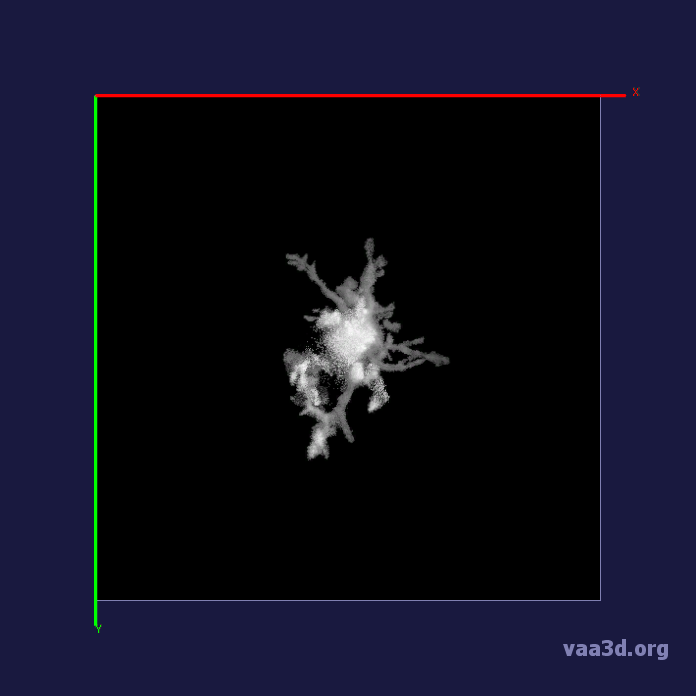

In our experiments, we compare the coupled TuFF-BFF microglia segmentation results with those given by L2S [21] and the Chan-Vese segmentation method [22]. The groundtruth in 3D was attained by manually tracing the object slice by slice from the z-stack. It must be noted that this was done by eye and could have some error. Figure 2 shows the visual comparison of the segmentation results for our dataset. Our result shown on the third column captures both the soma and processes. Figure 3 shows the Dice coefficient comparison of each segmentation method to the ground truth. Since the soma is much larger than the fine processes in the microglia, the processes have less volumetric impact on the similarity score. As explained in Section 1, segmenting the processes is important for quantifying the extension from the soma and its volume of surveillance. We use the Dice coefficient to quantitatively compare the ramification by taking the convex hull of the resulting segmentation. The Dice coefficient is a similarity measure that is computed using with where is the ground truth and is the compared image.

From Figure 4, the average Dice score for coupled TuFF-BFF was 0.77, compared to 0.53 for L2S [21] and .58 for Chan-Vese [22]. It must be noted that L2S required manual user initialization for each 2D image in the stack. While the Chan-Vese method has automatic seed selection, our coupled TuFF/BFF method was the only method that was a true 3D segmentation algorithm. L2S could not consistently capture the entire processes due to the intensity inhomogeneity throughout the object and background noise. The Chan-Vese segmentation could capture the extensions of the processes but did not work well with noise and attained false positives in the reconstruction. Since our method uses the tubular and blob information of the object to separate foreground and background, the segmentation only evolved within the object boundaries.